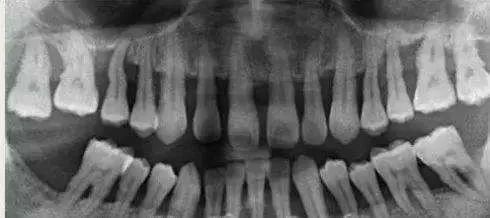

2、牙龈炎没有骨的破坏,所以X线片上没有骨吸收的情况。而牙周炎X线片上可见牙槽嵴的高度降低,呈水平型吸收,也可出现近牙根面的牙槽骨吸收,呈垂直或者角形骨吸收,这种骨的吸收,临床上表现为骨下袋。